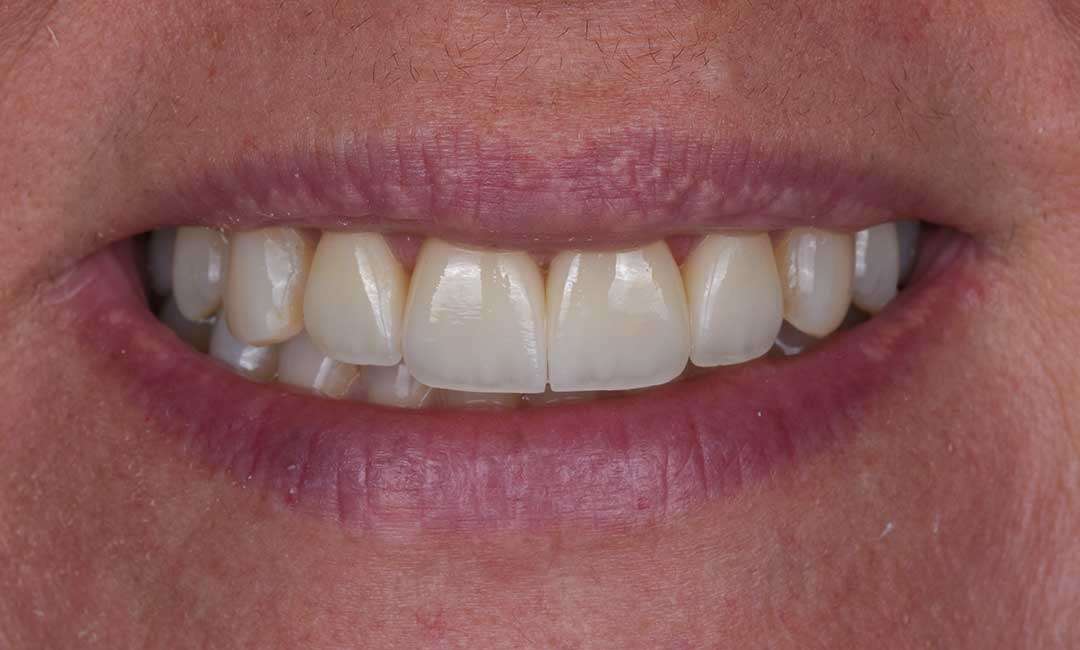

after

Before And After Full MouthRehabilitation Treatment